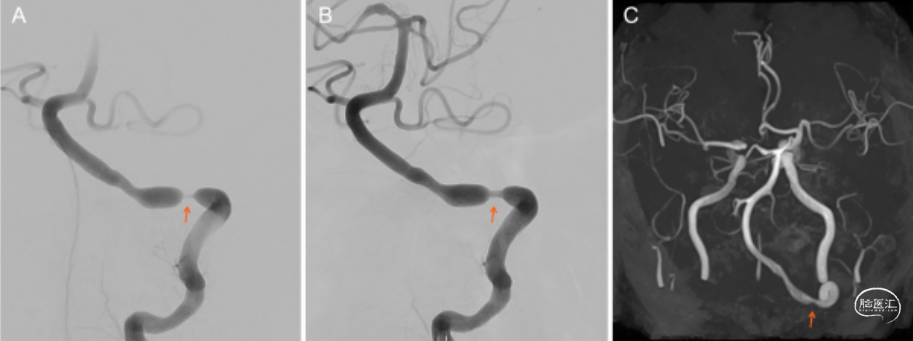

86岁女患,既往高血压、高血脂、风湿病史,突发头晕呕吐来诊。3月前开始口服糖皮质激素(泼尼松龙1mg+阿司匹林100mg)。影像学资料见图3。化验检查提示血沉增快,crp增高,考虑GCA可能性大,给予阿司匹林+氯吡格雷双联抗血小板治疗,阿加曲班抗凝治疗,颞动脉活检确诊巨细胞动脉炎(GCA),加用糖皮质激素治疗。患者症状仍进展。入院23天行椎动脉球囊扩张成形术(图4),手术顺利,术后患者症状改善。随访良好(图4)。

图4. A:术前造影可见左侧椎动脉串联重度狭窄;B:行球囊扩张成形术后狭窄改;C:术后3个月随访MRA可见椎动脉轻度狭窄,较前改善。